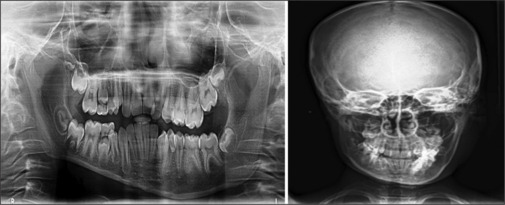

CHH is a rare developmental pathology and often presents a diagnostic dilemma to a clinician. It is characterized by marked unilateral overgrowth of hard and soft tissues of the face that is present since birth and advances with age, mostly till puberty. Though aetiology remains unknown, several factors could be considered including hormonal imbalances, diseases involving the neural system, vascular conditions, lymphatic abnormalities, mechanical influences and congenital syphilis. Hence, desired investigations should be done to rule out syndromes causing facial asymmetry. Since, management is considered when aesthetics are a prime concern, it should be planned only after growth cessation. We, hereby, present a case of 10-year-old male patient reported with chief complaint of asymmetry on left side of face from birth to supplement existing clinical knowledge.